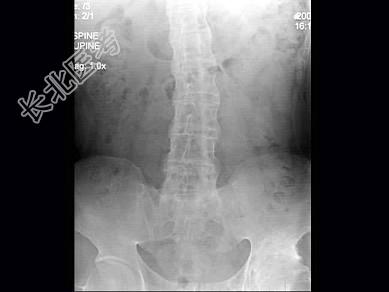

- 单项选择题男,41岁, 腰部酸肿不适10多年,近年加重, 腰部活动受限,晨僵1年, 腰椎正侧位片如图,最可能的诊断是 ( )